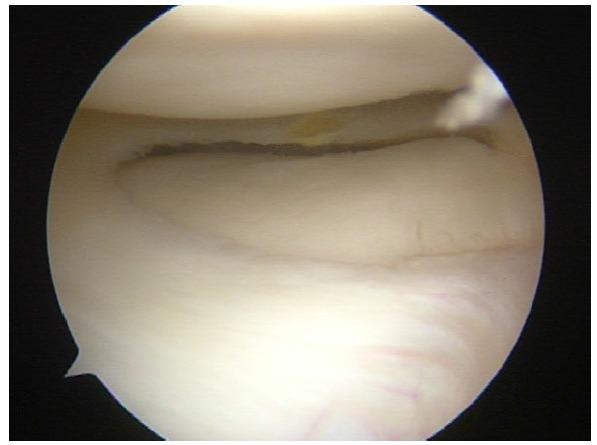

The glenohumeral joint is a ball-and-socket joint that is inherently unstable and thus, susceptible to dislocation. The traditional and most common anatomic finding is the Bankart lesion (anterior-inferior capsule labral complex avulsion), but there is a wide variety of anatomic alterations that can cause shoulder instability or may be present as a concomitant injury or in combination, including bone loss (glenoid or humeral head), complex capsule-labral tears, rotator cuff tears, Kim´s lesions (injuries to the posterior-inferior labrum) and rotator interval pathology.

Due to the complex anatomy of the shoulder and the large range of movement of this joint, a wide variety of anatomic injuries and conditions can lead to shoulder instability, specially present in young population. Recognizing and treating all of them including Bankart repair, capsule-labral plicatures, SLAP repair, circumferential approach to pan-labral lesions, rotator interval closure, rotator cuff injuries and HAGL lesion repair is crucial to achieve the goal of a stable, full range of movement and not painful joint.

盂肱关节是球窝关节,本质上不稳定,因此易发生脱位。传统且最常见的解剖学发现是Bankart损伤(前下关节囊盂唇复合体撕脱),但存在多种可导致肩部不稳定或可能作为伴随损伤出现或合并存在的解剖学改变,包括骨质流失(肩胛盂或肱骨头)、复杂的关节囊盂唇撕裂、肩袖撕裂、Kim损伤(后下盂唇损伤)和旋转间隙病变。

由于肩部解剖结构复杂且该关节活动范围大,多种解剖学损伤和病症可导致肩部不稳定,尤其在年轻人群中常见。识别并治疗所有这些损伤,包括Bankart修复、关节囊盂唇折叠术、SLAP修复、全盂唇病变的圆周入路、旋转间隙闭合、肩袖损伤和HAGL损伤修复,对于实现稳定、全范围活动且无痛关节的目标至关重要。